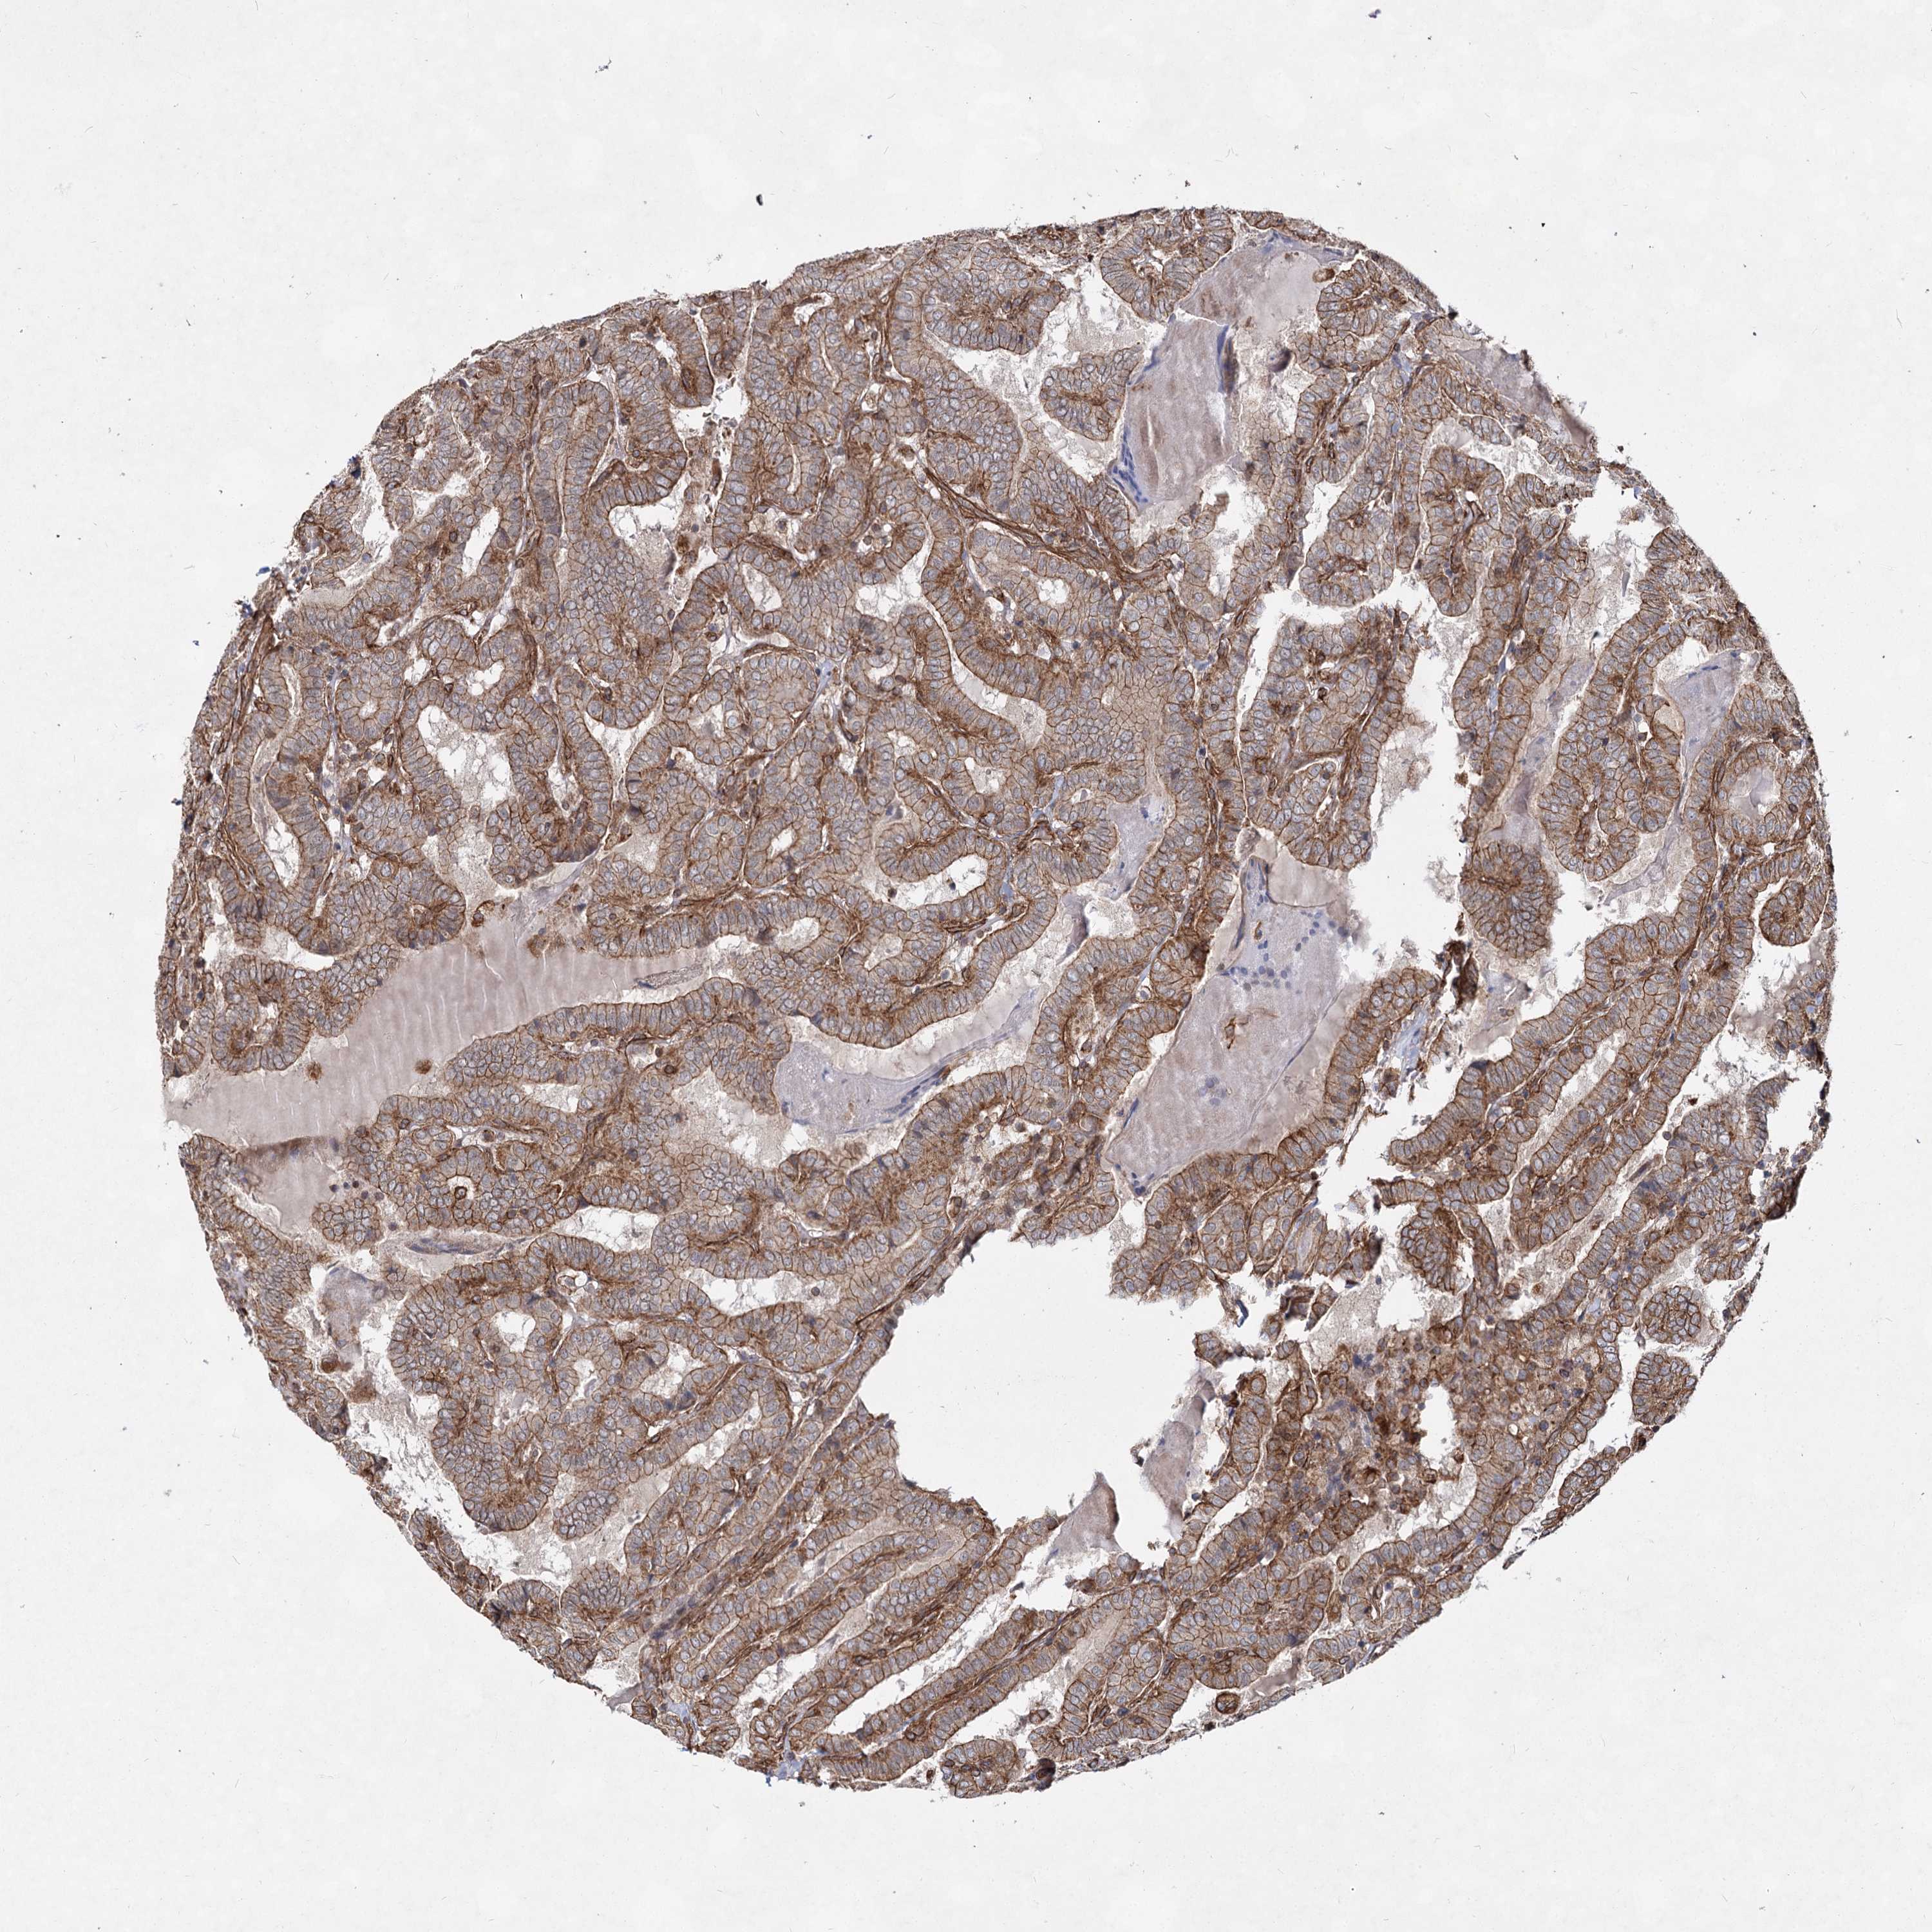

THYROID CANCER - Protein expressioni

A mouse-over function shows sample information and annotation data. Click on an image to view it in a full screen mode. Samples can be filtered based on level of antibody staining by selecting one or several of the following categories: high, medium, low and not detected. The assay and annotation is described here.

Note that samples used for immunohistochemistry by the Human Protein Atlas do not correspond to samples in the TCGA dataset.

Antibody stainingi

Antibody staining in the annotated cell types in the current human tissue is reported as not detected, low, medium, or high, based on conventional immunohistochemistry profiling in selected tissues. This score is based on the combination of the staining intensity and fraction of stained cells.

Each image is clickable and will lead to virtual microscopy that enables deeper exploration of all samples and also displays staining intensity scores, fraction scores and subcellular localization as well as patient and tissue information for each sample.

Antibody HPA038143

Antibody HPA038144

Staining

High

Medium

Low

Not detected

Intensity

Strong

Moderate

Weak

Negative

Quantity

>75%

75%-25%

<25%

None

Location

Nuclear

Cytoplasmic/membranous

Cytoplasmic/membranous,nuclear

Papillary adenocarcinoma, NOS

Follicular adenoma carcinoma, NOS